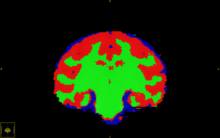

Segmentation of major tissue classes in for vervet subject